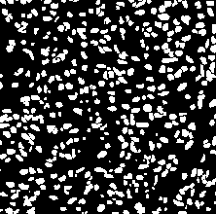

Microscopic image segmentation is a challenging task, wherein the objective is to assign semantic labels to each pixel in a given microscopic image. While convolutional neural networks (CNNs) form the foundation of many existing frameworks, they often struggle to explicitly capture long-range dependencies. Although transformers were initially devised to address this issue using self-attention, it has been proven that both local and global features are crucial for addressing diverse challenges in microscopic images, including variations in shape, size, appearance, and target region density. In this paper, we introduce SA2-Net, an attention-guided method that leverages multi-scale feature learning to effectively handle diverse structures within microscopic images. Specifically, we propose scale-aware attention (SA2) module designed to capture inherent variations in scales and shapes of microscopic regions, such as cells, for accurate segmentation. This module incorporates local attention at each level of multi-stage features, as well as global attention across multiple resolutions. Furthermore, we address the issue of blurred region boundaries (e.g., cell boundaries) by introducing a novel upsampling strategy called the Adaptive Up-Attention (AuA) module. This module enhances the discriminative ability for improved localization of microscopic regions using an explicit attention mechanism. Extensive experiments on five challenging datasets demonstrate the benefits of our SA2-Net model. Our source code is publicly available at \url{https://github.com/mustansarfiaz/SA2-Net}.